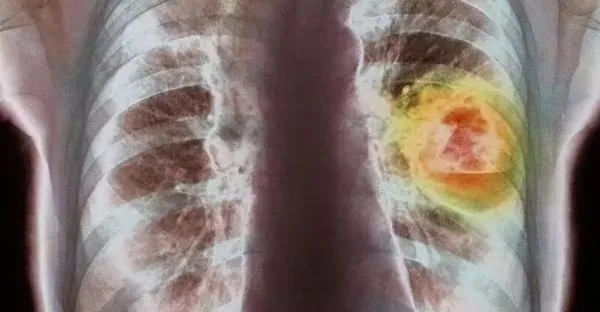

提醒:肺癌會發出的第一個信號,通常在喉嚨上,很多人都沒放心上

提醒:肺癌發出的第一個信號,通常在喉嚨上,很多人都沒放心上